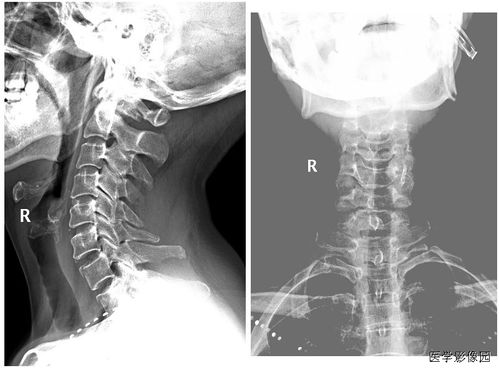

診斷手段:主要是根據(jù)臨床表現(xiàn)加上影像學(xué)檢查診斷。 (1) X線片:凡懷疑骨折者應(yīng)常規(guī)行X線檢查。

可發(fā)現(xiàn)臨床上難以發(fā)現(xiàn)的不完全骨折、深部骨折、關(guān)節(jié)內(nèi)骨折和撕脫骨折,臨床上明確骨折者也應(yīng)行X線檢查明確骨折類型及具體 情況,以指導(dǎo)治療。 (2) CT:對于骨折不明確但又不能排除者、脊柱骨折可能壓迫脊髓神經(jīng)根者及復(fù)雜骨折者 均應(yīng)行CT檢查。